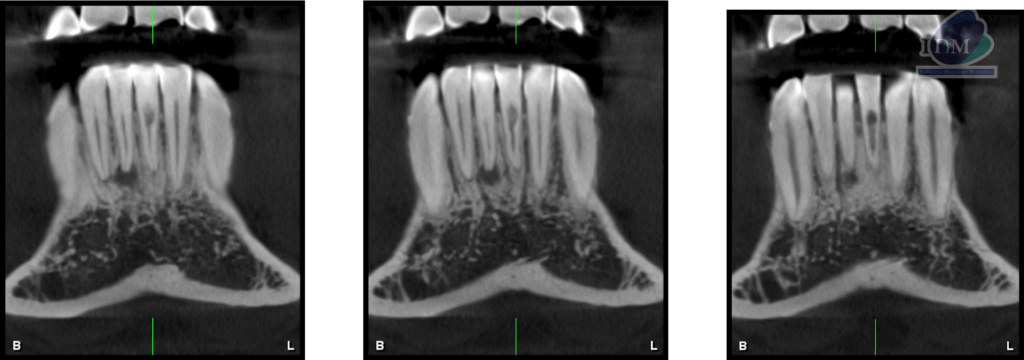

A la evaluación de la tomografía computarizada cone beam de campo mediano se observa en los cortes axiales, transaxialres y tangenciales la presencia de una imagen hipodensa que se localiza a nivel de tercio cervical de la pieza 31 por debajo del límite amelocementario en la superficie lingual la cual se comunica con el conducto pulpar ocasionando la alteración en su morfología, finalmente se observa un discreto ensanchamiento del espacio para el ligamento periodontal apical, compatible con reabsorción cervical invasiva (RCI)

CORTES TRANSAXIALES